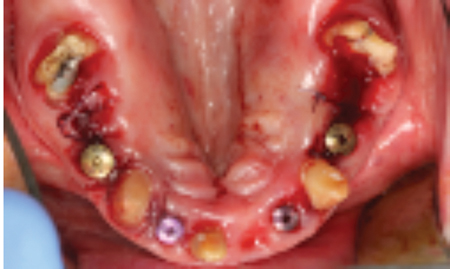

This article describes the treatment planning steps involved in creating a dental implant solution for a case of a failing dentition, making use of hopeless teeth and tooth roots) to serve as temporary abutments for a fixed-provisional prosthesis, while maintaining as much of the natural dentition as possible. The goal was to provide chewing efficiency and patient comfort during the osseointegration healing period while simultaneously preventing premature loading of newly placed dental implants as the patient is transitioned to the final definitive prostheses.

In this article we will highlight the reverse strategy of using ‘hopeless teeth and/or tooth roots to help safeguard newly placed dental implants’ from premature loading during the osseointegration period by serving as temporary abutments for fixed-partial temporary prostheses. These provisional prostheses can accept occlusal load while facilitating a smooth transition to final prosthesis. As such, the ‘rush to finish’ becomes less of a factor.

The final treatment plan would require implants in the #16, 14, 12, 22, 24 and 26 positions. The fixed provisional prosthesis would make use of provisional abutments on #17 and 27, 13, 23 and 11. The plan would involve serial extractions and grafting procedures to preserve bone volume in the ideal sites while avoiding any load on the newly grafted sites using strategic teeth to serve as provisional abutments. Patient accepted this solution and agreed to keep teeth #13 and #23. Benefits include cuspid rise occlusion, bone preservation and proprioception (also to minimize the significant risk with adjacent implants in the anterior zone).

- Extraction of #16, 12, 22 and 26. (Socket grafting #16, and 26 to preserve existing bone volume).

- Immediate implant placement in sites #12, 22, 14 and 24.

- Reassess healing clinically and radiographically over a 4-6 month healing period.